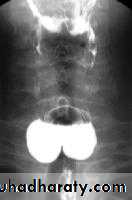

LEFT: Dilated esophagus (arrows) appears as long, well-defined structure paralleling heart RIGHT: Dilated esophagus usually deviates to right. Narrowing (arrow) at hiatus.